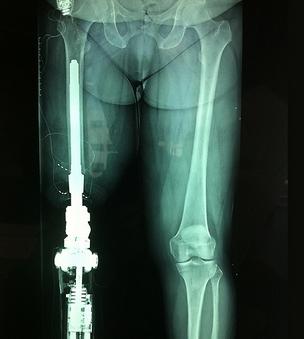

在中國(guó),需要假肢醫(yī)療設(shè)備的人有很多,但是傳統(tǒng)假肢造價(jià)高,還容易引起并發(fā)癥,導(dǎo)致這一需求長(zhǎng)時(shí)間得不到完善的解決。好在近些